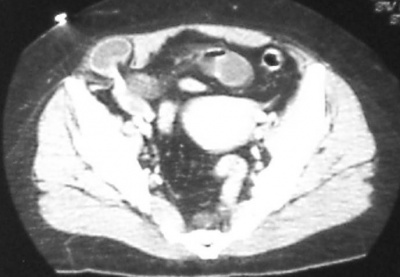

האבחנה לעתים קרובות קשה, מכיוון שהבקע פורץ בין השרירים ולא מתחת לעור, וכמו-כן הוא נוטה לכיוון לטרלי, כך שקשה להעריך את מוצאו. בקע זה נוטה להיכלא ולעבור סטרנגולציה. בדרך כלל החולים מספרים על אי-נוחות או כאבים בשיעול. לעתים הסיפור הקליני מלווה בהקאות או בבחילות ואז קשה להבדיל בין הבקע לבין מחלות תוך-בטניות אחרות. האבחנה מתבצעת על-ידי מישוש גוש בבטן במקום המתאים, שניתן להחזירו לבטן. לאחר ההחזרה ניתן למשש את הפגם בפסציה. לעיתים הבקעה מאובחן בעזרת CT המבוצע עקב כאבי בטן מקומיים (תצלום 2.13 )